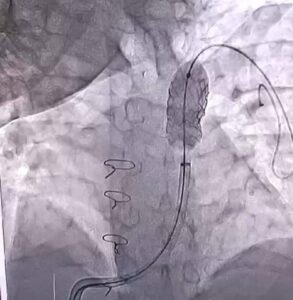

في إنجاز طبي متميز، تمكنت أكاديمية قلب مستشفى المبرة بمصر القديمه، من إجراء عملية جراحية نادرة ومعقدة لمريضة تعاني من ضيق حاد تفرعي في الشريان الرئوي الأيمن والأيسر، وتمت العملية بنجاح تحت قيادة الأطباء المتخصصين ا. د. محمد صبري الحديني و ا. د. علي جلال بحيري.

وقال د. محمد صبري الحديني، استشاري القلب والأوعية الدموية في أكاديمية قلب مستشفى المبرة: “كانت هذه حالة نادرة ومعقدة للغاية، حيث عانت المريضة من ضيق حاد في التفرعات الرئيسية للشريان الرئوي. وقمنا بإجراء توسيع للتضيقات وزرع دعامتين تفرعيتين، وتمت العملية بنجاح كامل”.